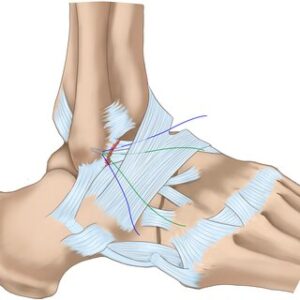

– Reparación ligamentosa con refuerzo: En esta técnica se intenta reparar los ligamentos previamente dañados, realizando una sutura directa, a la que añadimos un refuerzo dado que el tejido original se encuentra debilitado.

– Reconstrucción ligamentosa: En esta opción reconstruimos los ligamentos desde cero. Se emplean injertos del propio paciente o de un donante. Solemos emplear esta técnica cuando tenemos dudas sobre la viabilidad el tejido original o cuando otras técnicas han fracasado.

Aunque la recuperación tras la cirugía debe ser lenta y cuidadosa, los resultados de estas técnicas suelen ser satisfactorios, llegando incluso a permitir volver a una practica deportiva en un alto porcentaje de pacientes tratados.